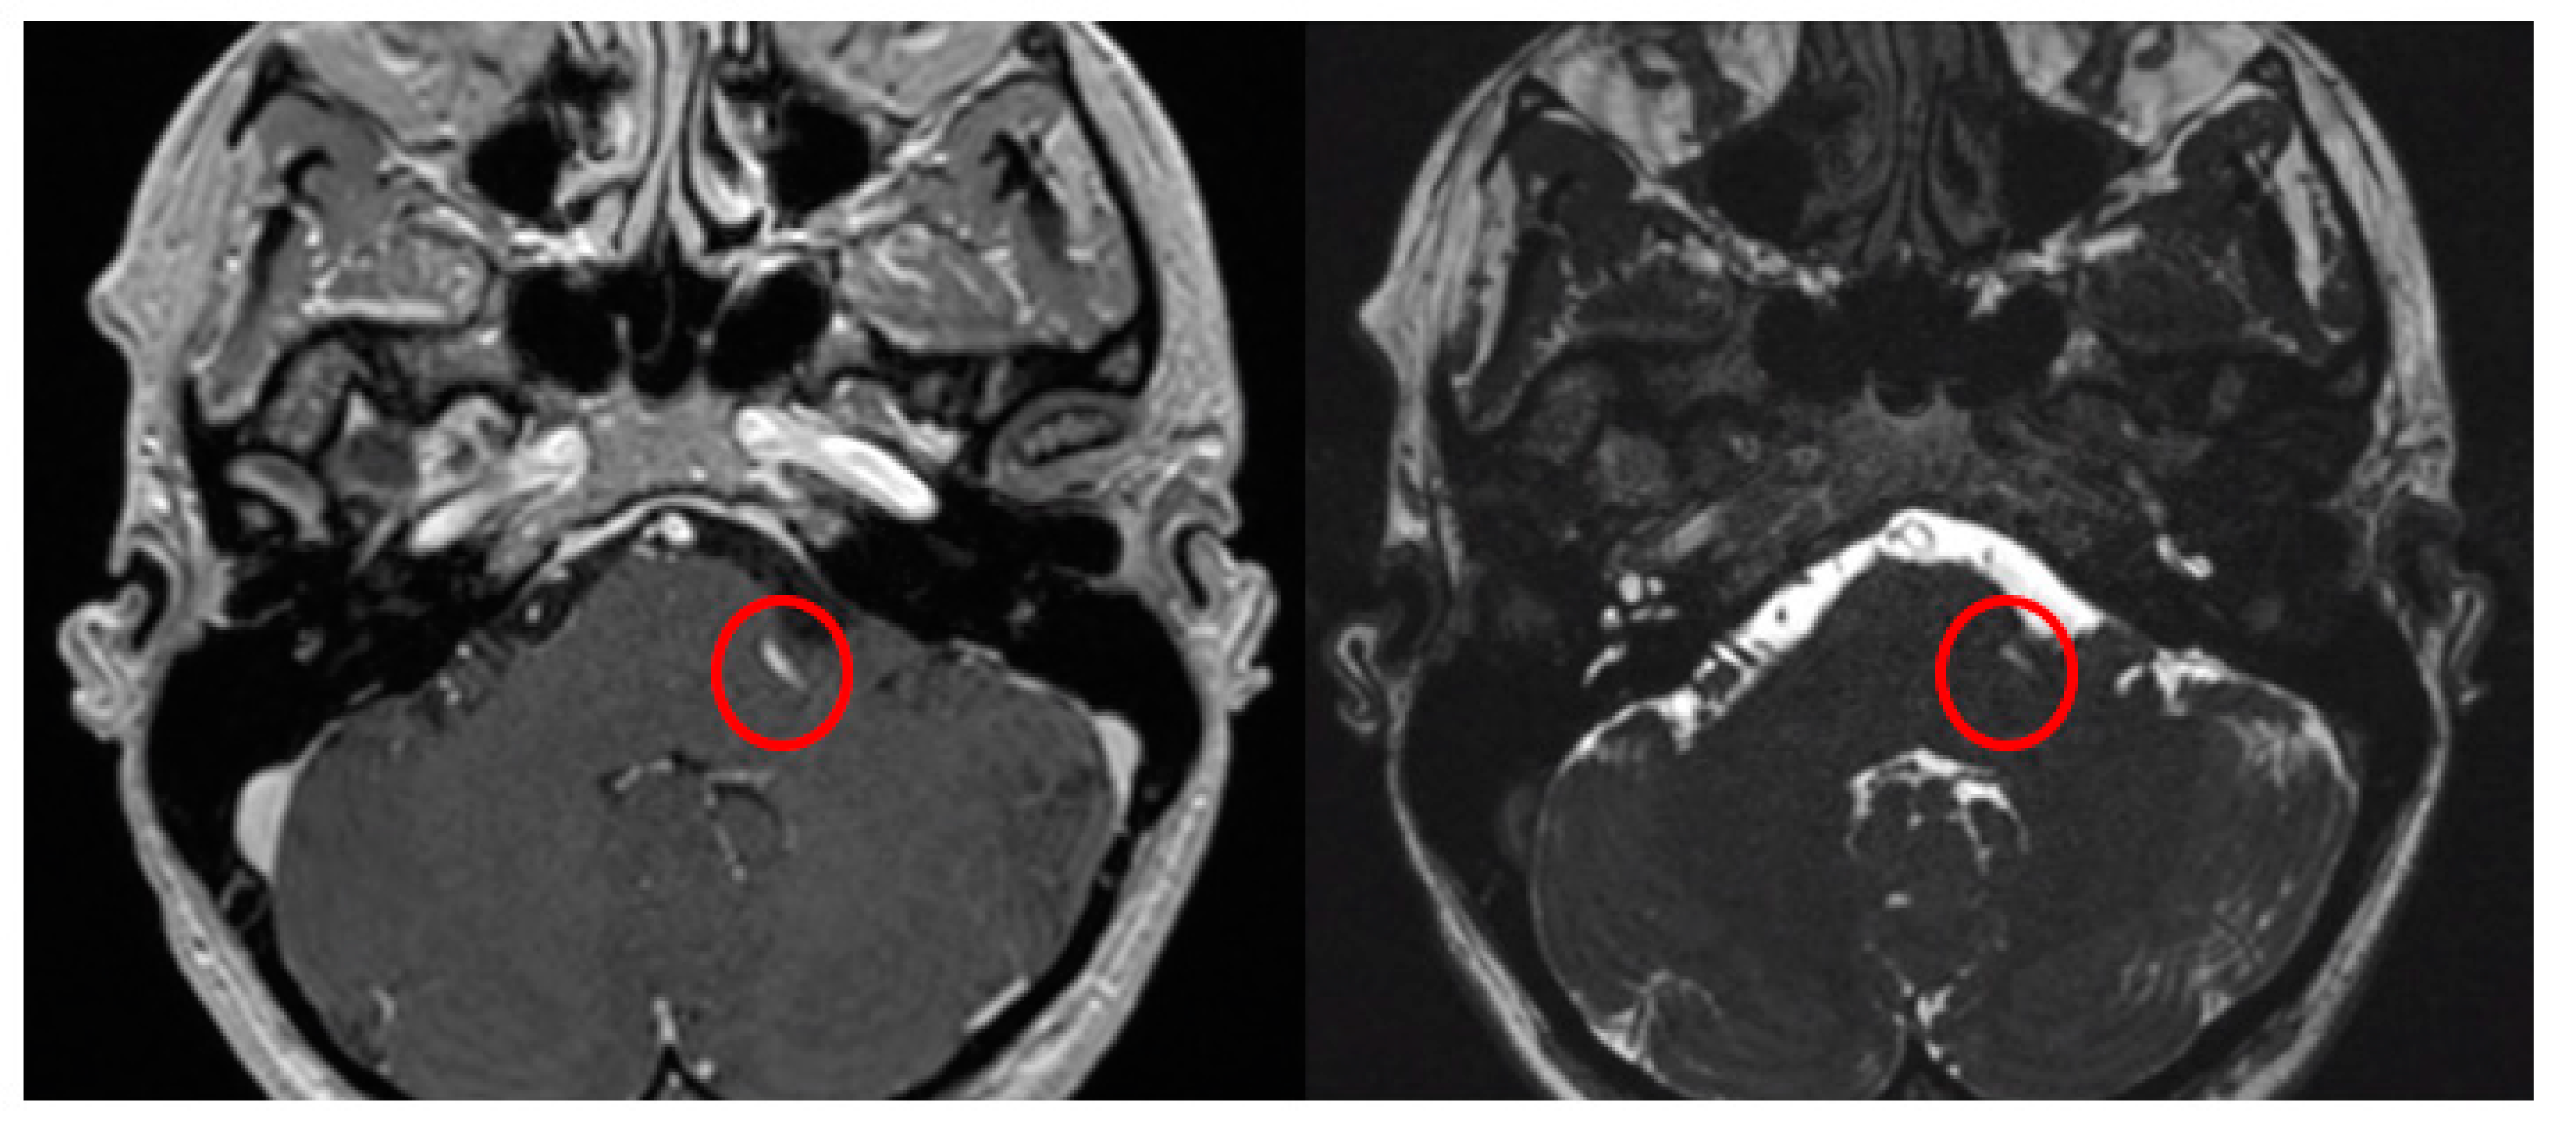

The Prevedello Sign is the identification of an arterial loop enfolded by the pons near the exit of the facial nerve, in the brainstem. This finding is best visualized in T1WI with contrast and in FIESTA acquisitions of MRI sequences (Figure 3).

Figure 3.

Axial view of MRI in T1WI with gadolinium and FIESTA sequences demonstrating the presence of the Prevedello sign (an arterial loop attached to the pons near the exit of the facial nerve), highlighted by the red circles.